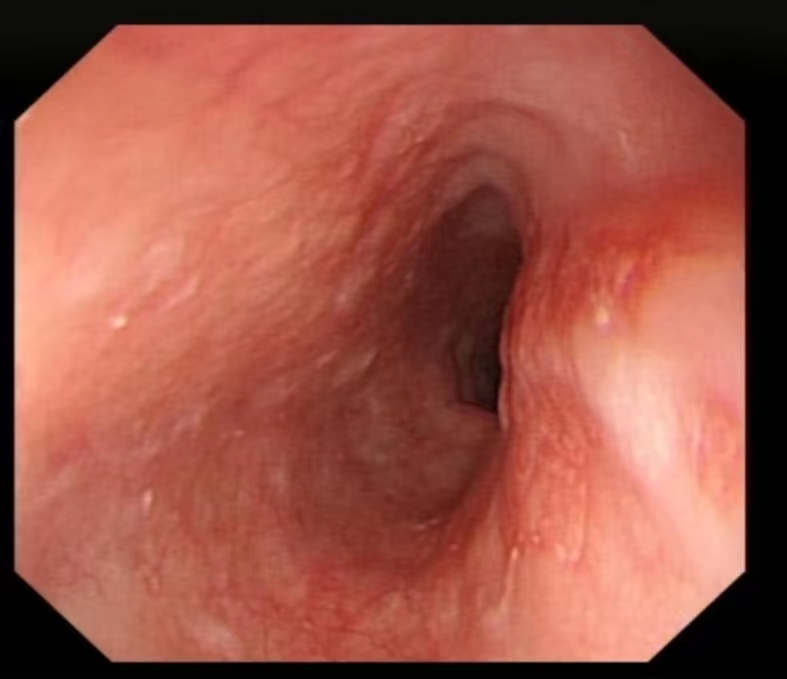

咽喉部肿瘤